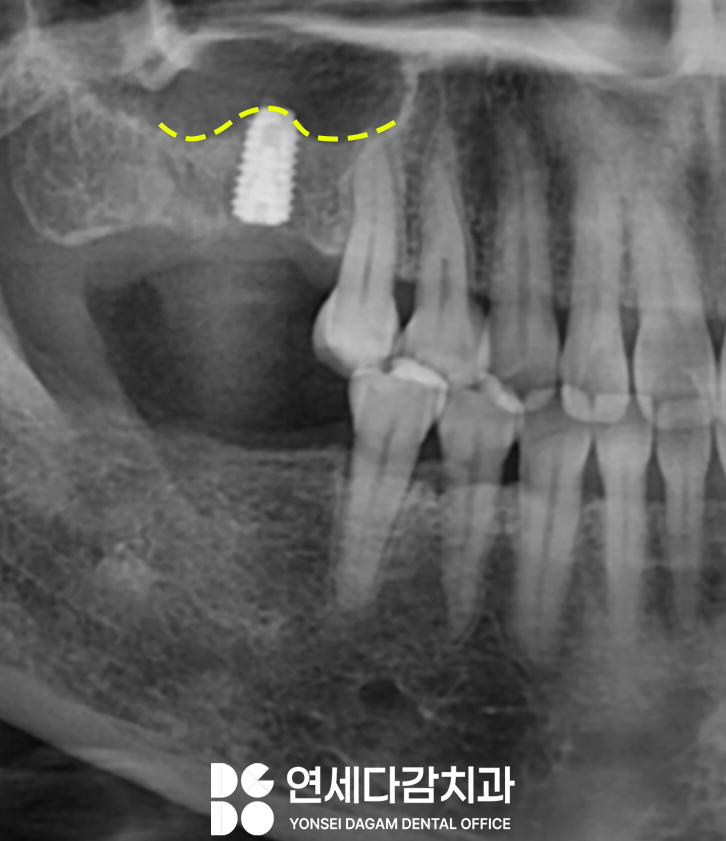

경찰병원역 치과 에서 진단 결과

치조정 접근법으로

가능할 것으로 판단되었습니다.

수직적 골량이 심하게

부족하지 않는 이상

치조정 접근 방법으로 진행하는 것이

치유 과정이 더 짧아질 수 있어

환자 입장에서 덜 고생하실 수 있습니다.

수압 거상 방식으로 진행되었습니다.

기존 수직골이 3미리도 안되던 뼈가

거상 후 3배 정도 많아진 것을

엑스레이를 통해 알 수 있었습니다.